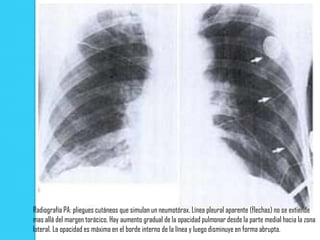

   Los tejidos blandos que cubren la zona se pliegan y la

aparente opacidad del tejido pulmonar aumenta hacia los

lados en forma gradual hasta llegar a un borde en el que

disminuye en forma brusca.

   Este borde representa el margen lateral de los tejidos

plegados.

   A menudo la vasculatura pulmonar es visible en la parte

distal a la línea del pliegue cutáneo

Radiografía PA: pliegues cutáneos que simulan un neumotórax. Línea pleural aparente (flechas) no se extiende

mas allá del margen torácico. Hay aumento gradual de la opacidad pulmonar desde la parte medial hacia la zona

lateral. La opacidad es máxima en el borde interno de la línea y luego disminuye en forma abrupta.

Radiografía PA: plieguescutáneos que simulan un neumotórax. Línea pleural aparente (flechas) no se extiende mas allá del margen torácico. Hay aumento gradual de la opacidad pulmonar desde la parte medial hacia la zona lateral. La opacidad es máxima en el borde interno de la línea y luego disminuye en forma abrupta.